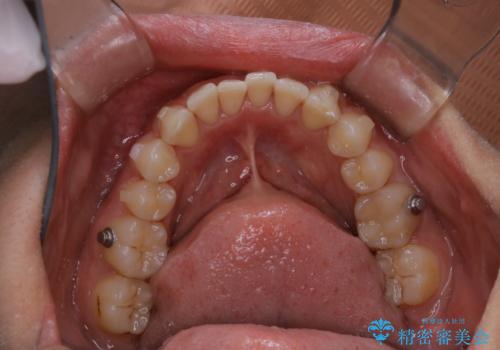

- インビザラインでの矯正治療中に、着色や汚れが気になるとのことでした。PMTC60分コースを行いました。

インビザライン治療中には、歯の表面にアタッチメント(効率的に歯の移動をするもの)を設定します。そのため歯ブラシでは届きにくい細かい部分などに、歯石や着色がついてしまうことがあります。着色などを放置していると、着色なのか、虫歯なのかの判別もしずらく正確にお口の中の状態を診断できません。

矯正治療中も定期的に歯科医院にてPMTCを受けて、お口のケアを行うことをおすすめします。